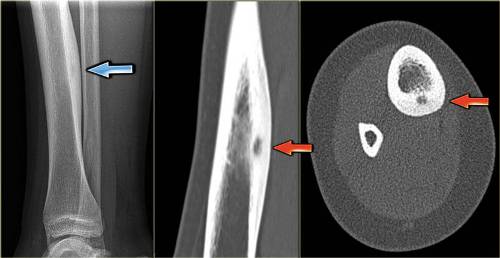

При диагностике следует дифференцировать остеому от солидной одонтомы, реактивных разрастаний костных тканей, оссифицированной фиброзной дисплазии, которые могут возникать в следствие инфекционных поражений или тяжелых травм. На начальных стадиях заболевания назначаются дополнительные методы исследований — рентгенография, информативная компьютерная томография. В зависимости от места расположения лечением данной доброкачественной опухоли занимаются челюстно-лицевые хирурги, нейрохирурги, травматологи.

Диагностика остеоид-остеомы включает рентгенографию, которая может показать характерные изменения в костной ткани, такие как небольшая луковичная область с остеосклерозом. В некоторых случаях может потребоваться компьютерная томография (КТ) для более точного определения размера и локализации опухоли. Также может быть назначено магнитно-резонансное исследование (МРТ) для оценки состояния мягких тканей вокруг опухоли.